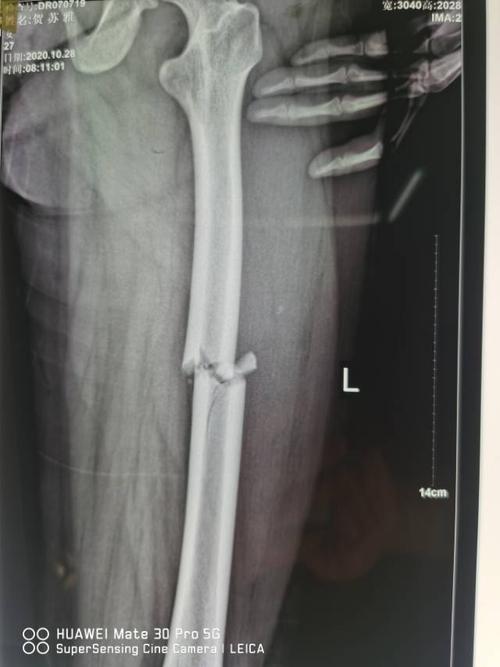

腹胀等伴随症状,未做特殊处理,随来我院就诊,门诊拍片示:左股骨干骨折

左股骨干骨折骨痂图片

股骨干骨折愈合好图片